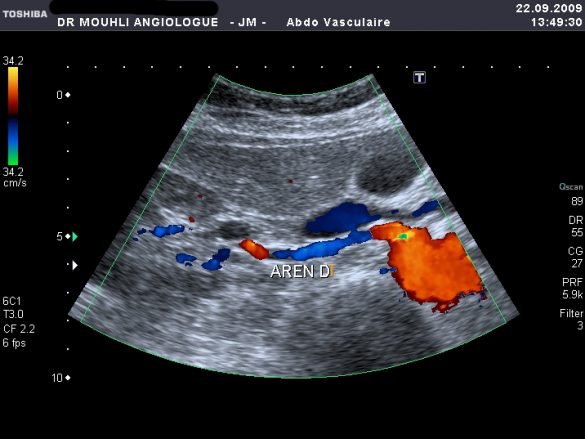

Voie endovasculaire stenting artere renale by jamel MOUHLI 9 juillet 2010 written by jamel MOUHLI 9 juillet 2010 0 comments 0 minutes read Bookmark 394 {flv}pose d un stentsur l artere renale{/flv} Post Views: 151 Share 0 FacebookTwitterPinterestEmail jamel MOUHLI Following Author previous post stenting artère rénale next post Infarctus du myocarde et Pontage aorto-coronaire You may also like Bookmark AORTIC VALVE REPAIR SUMMIT 24 octobre 2025 Bookmark Les médecins vasculaires (angiologues), les chirurgiens vasculaires et... 3 octobre 2022 Bookmark SYNDROME DE COCKETT OU SYNDROME DE MAY-THURNER 24 février 2022 Bookmark Thrombectomie endovasculaire opportune impérative pour des résultats post-AVC... 29 juin 2021 Bookmark Essai BEST endovasculaire versus meilleur traitement chirurgical chez... 10 juin 2021 Bookmark L’imagerie non invasive dans l’hypertension rénovasculaire 27 novembre 2020